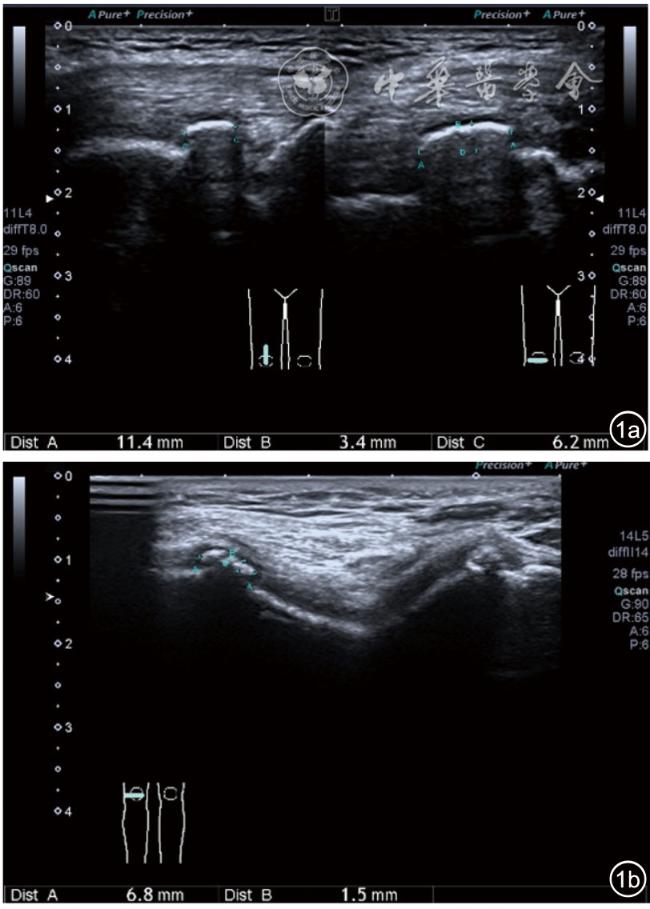

3.超声半定量评估。(1)骨赘超声半定量评估:患者仰卧位,膝关节伸直,探头纵切面置于膝关节内侧与外侧,自前向后移动探头以进行全面扫查。测量骨赘的厚度,并进行半定量分析。0级:无骨赘;1级:小骨赘,厚度<2 mm;2级:中等骨赘,厚度2.1~4.0 mm;3级:大骨赘,厚度>4.0 mm。(2)关节软骨超声半定量评估:患者仰卧位,膝关节完全屈曲。探头置于骨上方,检查股骨内侧髁、外侧髁和股骨滑车处关节软骨三个部位,分别进行横切面和纵切面检查,从近侧向远侧做全面扫查。检查时声束要垂直于股骨表面。关节软骨可按病变严重程度分为四级。0级:关节软骨呈均匀的无回声带,其浅侧和深侧边界清晰。1级:关节软骨浅侧边界不清和(或)内部回声增高。2级:①2A级,关节软骨局部变薄,缺损厚度<50%;②2B级,关节软骨局部变薄,缺损厚度>50%,但<100%。3级:关节软骨局部完全消失,伴或不伴有软骨下骨病变。(3)半月板突出分度:半月板外周缘与胫骨平台边缘之间的距离≥3 mm的突出视为病理变化,诊断为半月板周缘滑脱。按照突出程度分为三度:Ⅰ度,半月板外周缘与胫骨平台边缘之间的距离3~5 mm;Ⅱ度,半月板外周缘与胫骨平台边缘之间的距离>5~8 mm;Ⅲ度,半月板外周缘与胫骨平台边缘之间的距离8 mm以上。

2.膝关节静态结构治疗。动力平衡失调后,继发静态结构变化,出现内外侧副韧带、交叉韧带、脂肪垫、半月板等结构变化。这里介绍半月板与交叉韧带的处理。(1)膝关节静态结构半月板治疗。在膝关节骨关节炎中主要是突出和损伤。突出主要发生于膝内翻引起的内侧半月板突出,引起内侧副韧带的张力增高。内侧半月板与内侧副韧带相连,是引起膝关节内侧疼痛的主要原因之一。治疗主要是针刀剥离松解,部分损伤可行PRP注射。①半月板突出针刀剥离松解治疗。针刀治疗主要是松解和减压,缓解疼痛,不能复位。以内侧半月板突出治疗为例。患者平卧位,髋轻度外展外旋,膝关节屈曲30°,膝下垫一软枕。选用10 MHz超声探头,穿刺区域常规消毒,探头涂抹耦合剂后套入无菌手套碘伏消毒或使用无菌耦合剂。将探头置于患者皮肤表面,内侧关节间隙长轴扫查,找到半月板突出最高点,用25G针头,抽吸1%利多卡因3 ml逐层麻醉直到半月板。选用直径1 mm的Ⅰ型2号针刀从头侧向足侧方向在内侧副韧带与半月板之间,以及半月板内部进行剥离松解3~5刀拔出针刀(图13),局部压迫5分钟,无菌敷料覆盖。②半月板损伤PRP注射治疗。半月板损伤主要表现为髌下痛,伸膝加重,查体在髌下髌韧带与侧副韧带之间,沿关节间隙有固定或局限性压痛,伸膝过程中尤为明显。MRI可示半月板断裂、损伤。如果出现绞索,严重影响功能需手术治疗。半月板损伤治疗,以注射PRP修复为主。以内侧半月板后角损伤为例。患者俯卧位,治疗前准备同半月板突出针刀剥离松解治疗。选用25G注射针头,抽取1%利多卡因2 ml局部麻醉后,制取1.5 ml PRP,穿刺到达半月板撕裂处注射,注射完毕后出针(图14),局部压迫2分钟,无菌敷料覆盖。(2)膝关节静态结构交叉韧带治疗。膝关节骨关节炎交叉韧带损伤多为部分损伤,治疗早期主要为药物或PRP注射,效果不佳时针刀做止点松解。①后交叉韧带损伤药物注射治疗。主要治疗韧带肿胀、无明显断裂患者。患者俯卧位,膝关节伸直位。一般选用10 MHz超声探头,治疗前准备同半月板突出针刀剥离松解治疗。将探头置于患者皮肤表面,后交叉韧带长轴扫查,找到胫骨止点,选用22G长针头,抽吸1%利多卡因3 ml+曲安奈德10 mg,从头侧向足侧方向穿刺到后交叉韧带胫骨止点部位的韧带表面进行注射,注射结束拔出针头(图15),局部压迫2分钟,无菌敷料覆盖。②前交叉韧带损伤PRP注射治疗。患者仰卧位,膝关节伸直。选用10 MHz超声探头,治疗前准备同半月板突出针刀剥离松解治疗。将探头置于患者皮肤表面,短轴扫查,找到前交叉韧带胫骨止点,选用25G针头,抽吸1%利多卡因3 ml逐层麻醉直到韧带止点部位,制备PRP 3 ml注射到前交叉韧带显露部位,注射结束拔出针头(图16),局部压迫2分钟,无菌敷料覆盖。③前交叉韧带损伤针刀剥离松解治疗。体位与治疗前准备同前交叉韧带损伤PRP注射治疗。短轴扫查找到前交叉韧带胫骨止点,选用25G针头,抽吸1%利多卡因3 ml逐层麻醉直到韧带止点部位,选用直径0.6 mm的Ⅰ型2号针刀从外侧向内侧于前交叉韧带胫骨止点部位剥离松解3~5刀拔出针刀(图17),局部压迫5分钟,无菌敷料覆盖。

图18 超声引导下膝关节内症状性骨赘针刀剥离松解治疗